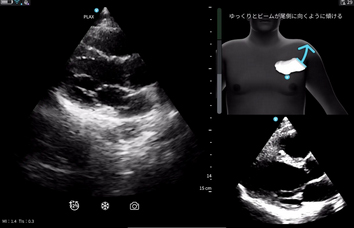

※Cardiac Guidance/ Interpretationの実際の画面

リアルタイムで操作者をサポートするガイド機能で,プローブ(探触子)の位置,角度,肋間操作,深度を画面上で指示し,より正確で高品質な画像取得をサポートする。さらに,画像品質のインジケータ機能を備えており,最適なスキャン画像が得られているか否かを判定する。また,一定レベル以上の品質を認識した際には,プローブを一定時間保持することで自動的に画像を保存する。Cardiac Guidanceの機能により,複雑な心エコー検査を簡便かつ正確に実施することが可能となり,臨床現場だけでなく,大学や基幹病院のトレーニングセンターでの教育利用にも「Vscan Air SL Ally」の導入が期待される。

※Cardiac Guidanceによる心エコー検査のリアルタイムガイド表示機能。Quality Meterで画像クオリティを確認,画面上部にはイラストとともに「時計回りにゆっくりと回転」などリアルタイムに様々なガイダンスが表示される。